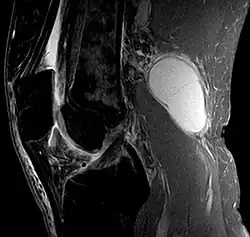

Baker's cyst on MRI, sagittal image -